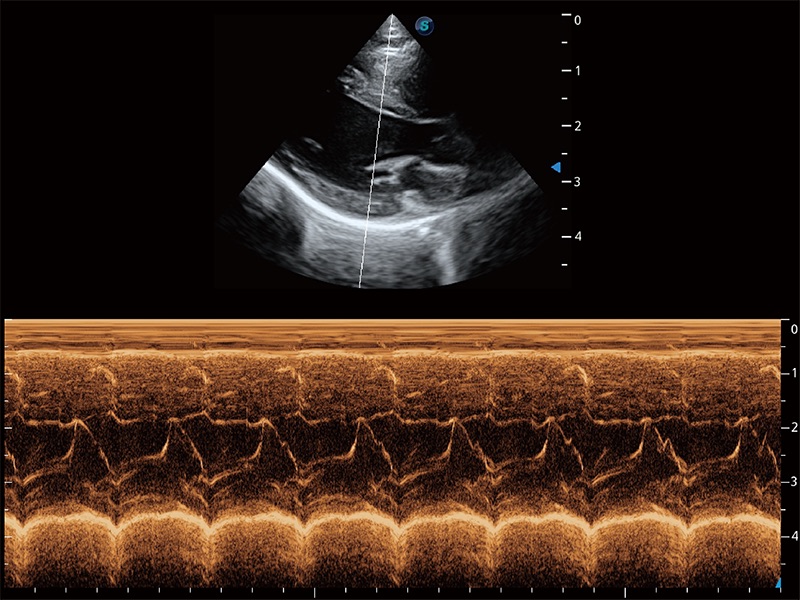

通過360度任意調(diào)節(jié)3條M型取樣線,在同一心動周期上觀察心臟不同位置的運動曲線,得到準確的心功能測量數(shù)據(jù),有效評估心肌運動及左心室功能。

ProPet 80 配備了豐富的心臟探頭群、先進的成像技術(shù)和專業(yè)的心臟測量工具,可幫助動物醫(yī)生為不同體型和生理結(jié)構(gòu)的動物提供心臟和心肌功能的全面評估。